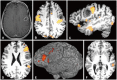

The imaging and clinical management of patients with brain tumor continue to evolve over time and now heavily rely on physiologic imaging in addition to high-resolution structural imaging. Imaging remains a powerful noninvasive tool to positively impact the management of patients with brain tumor. This article provides an overview of the current state-of-the art clinical brain tumor imaging. In this review, we discuss general magnetic resonance (MR) imaging methods and their application to the diagnosis of, treatment planning and navigation, and disease monitoring in patients with brain tumor. We review the strengths, limitations, and pitfalls of structural imaging, diffusion-weighted imaging techniques, MR spectroscopy, perfusion imaging, positron emission tomography/MR, and functional imaging. Overall this review provides a basis for understudying the role of modern imaging in the care of brain tumor patients.